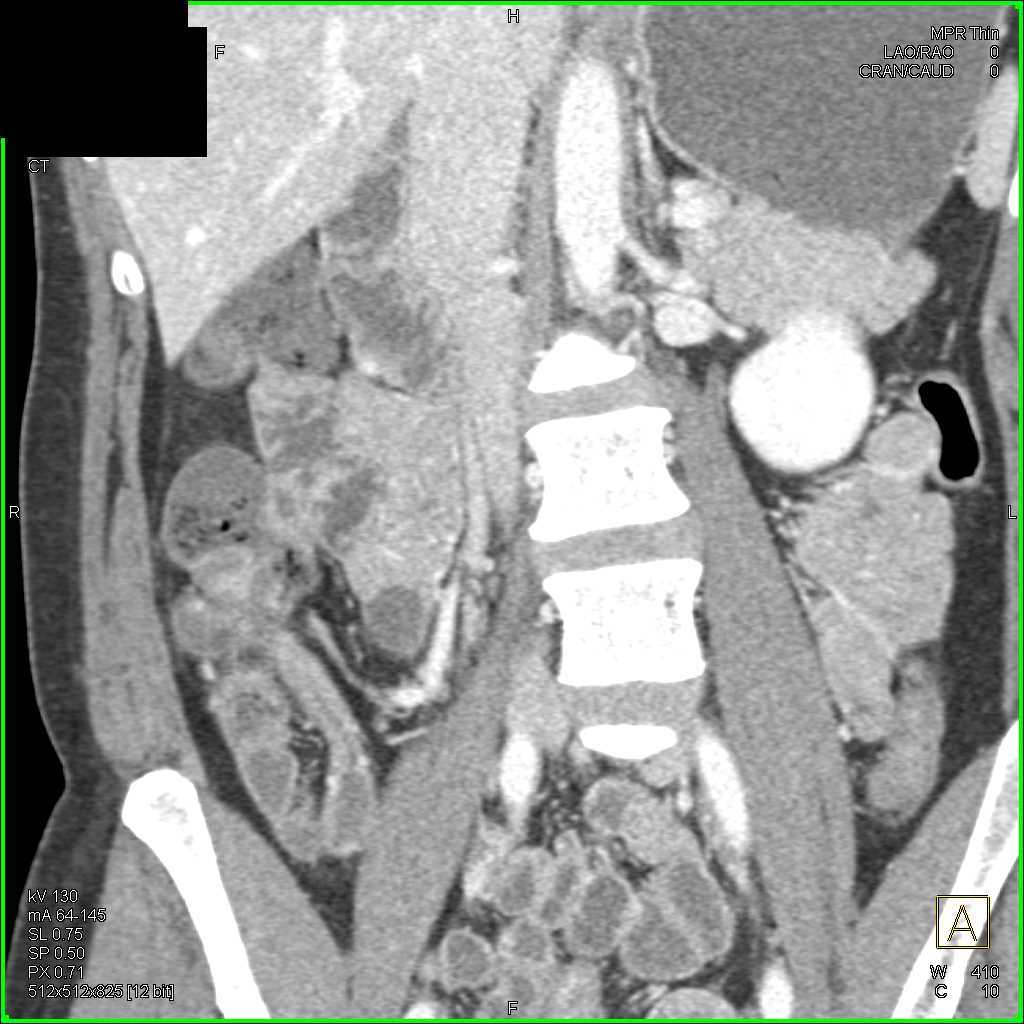

Carcinoid Tumor with Desmoplastic Reaction